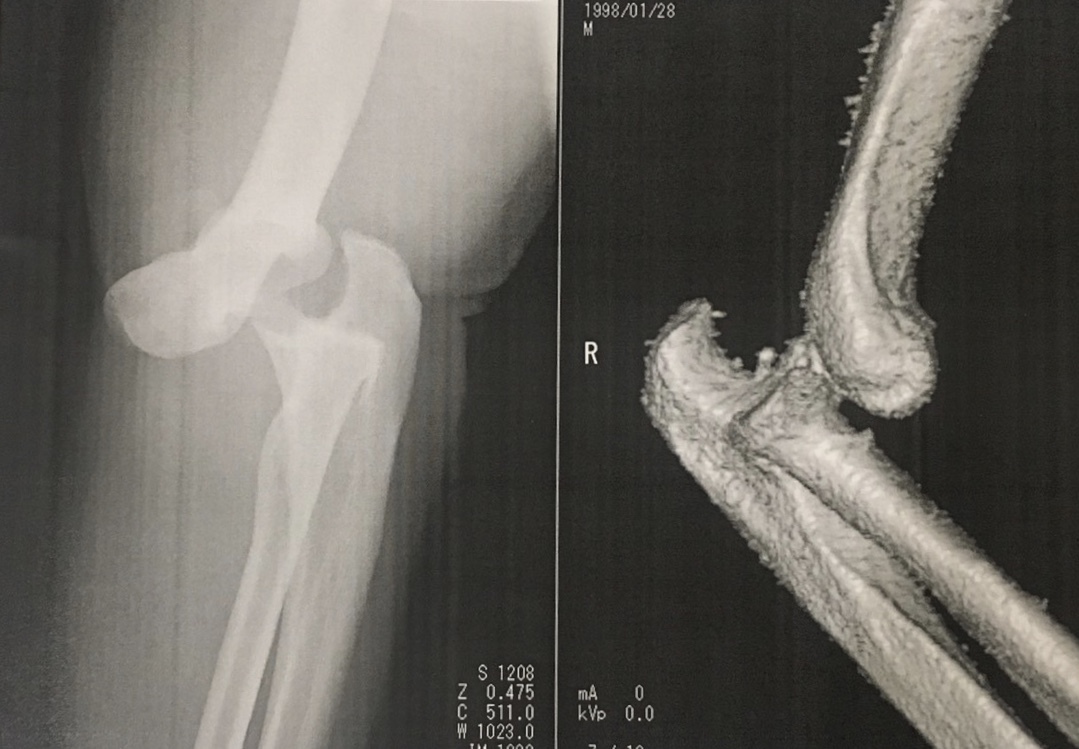

医療機関によるレントゲン、CT、MRI画像などを確認しながら医師の所見を基にリハビリ方針を決めて、各スタッフ間で情報共有して運営するよう心がけています。